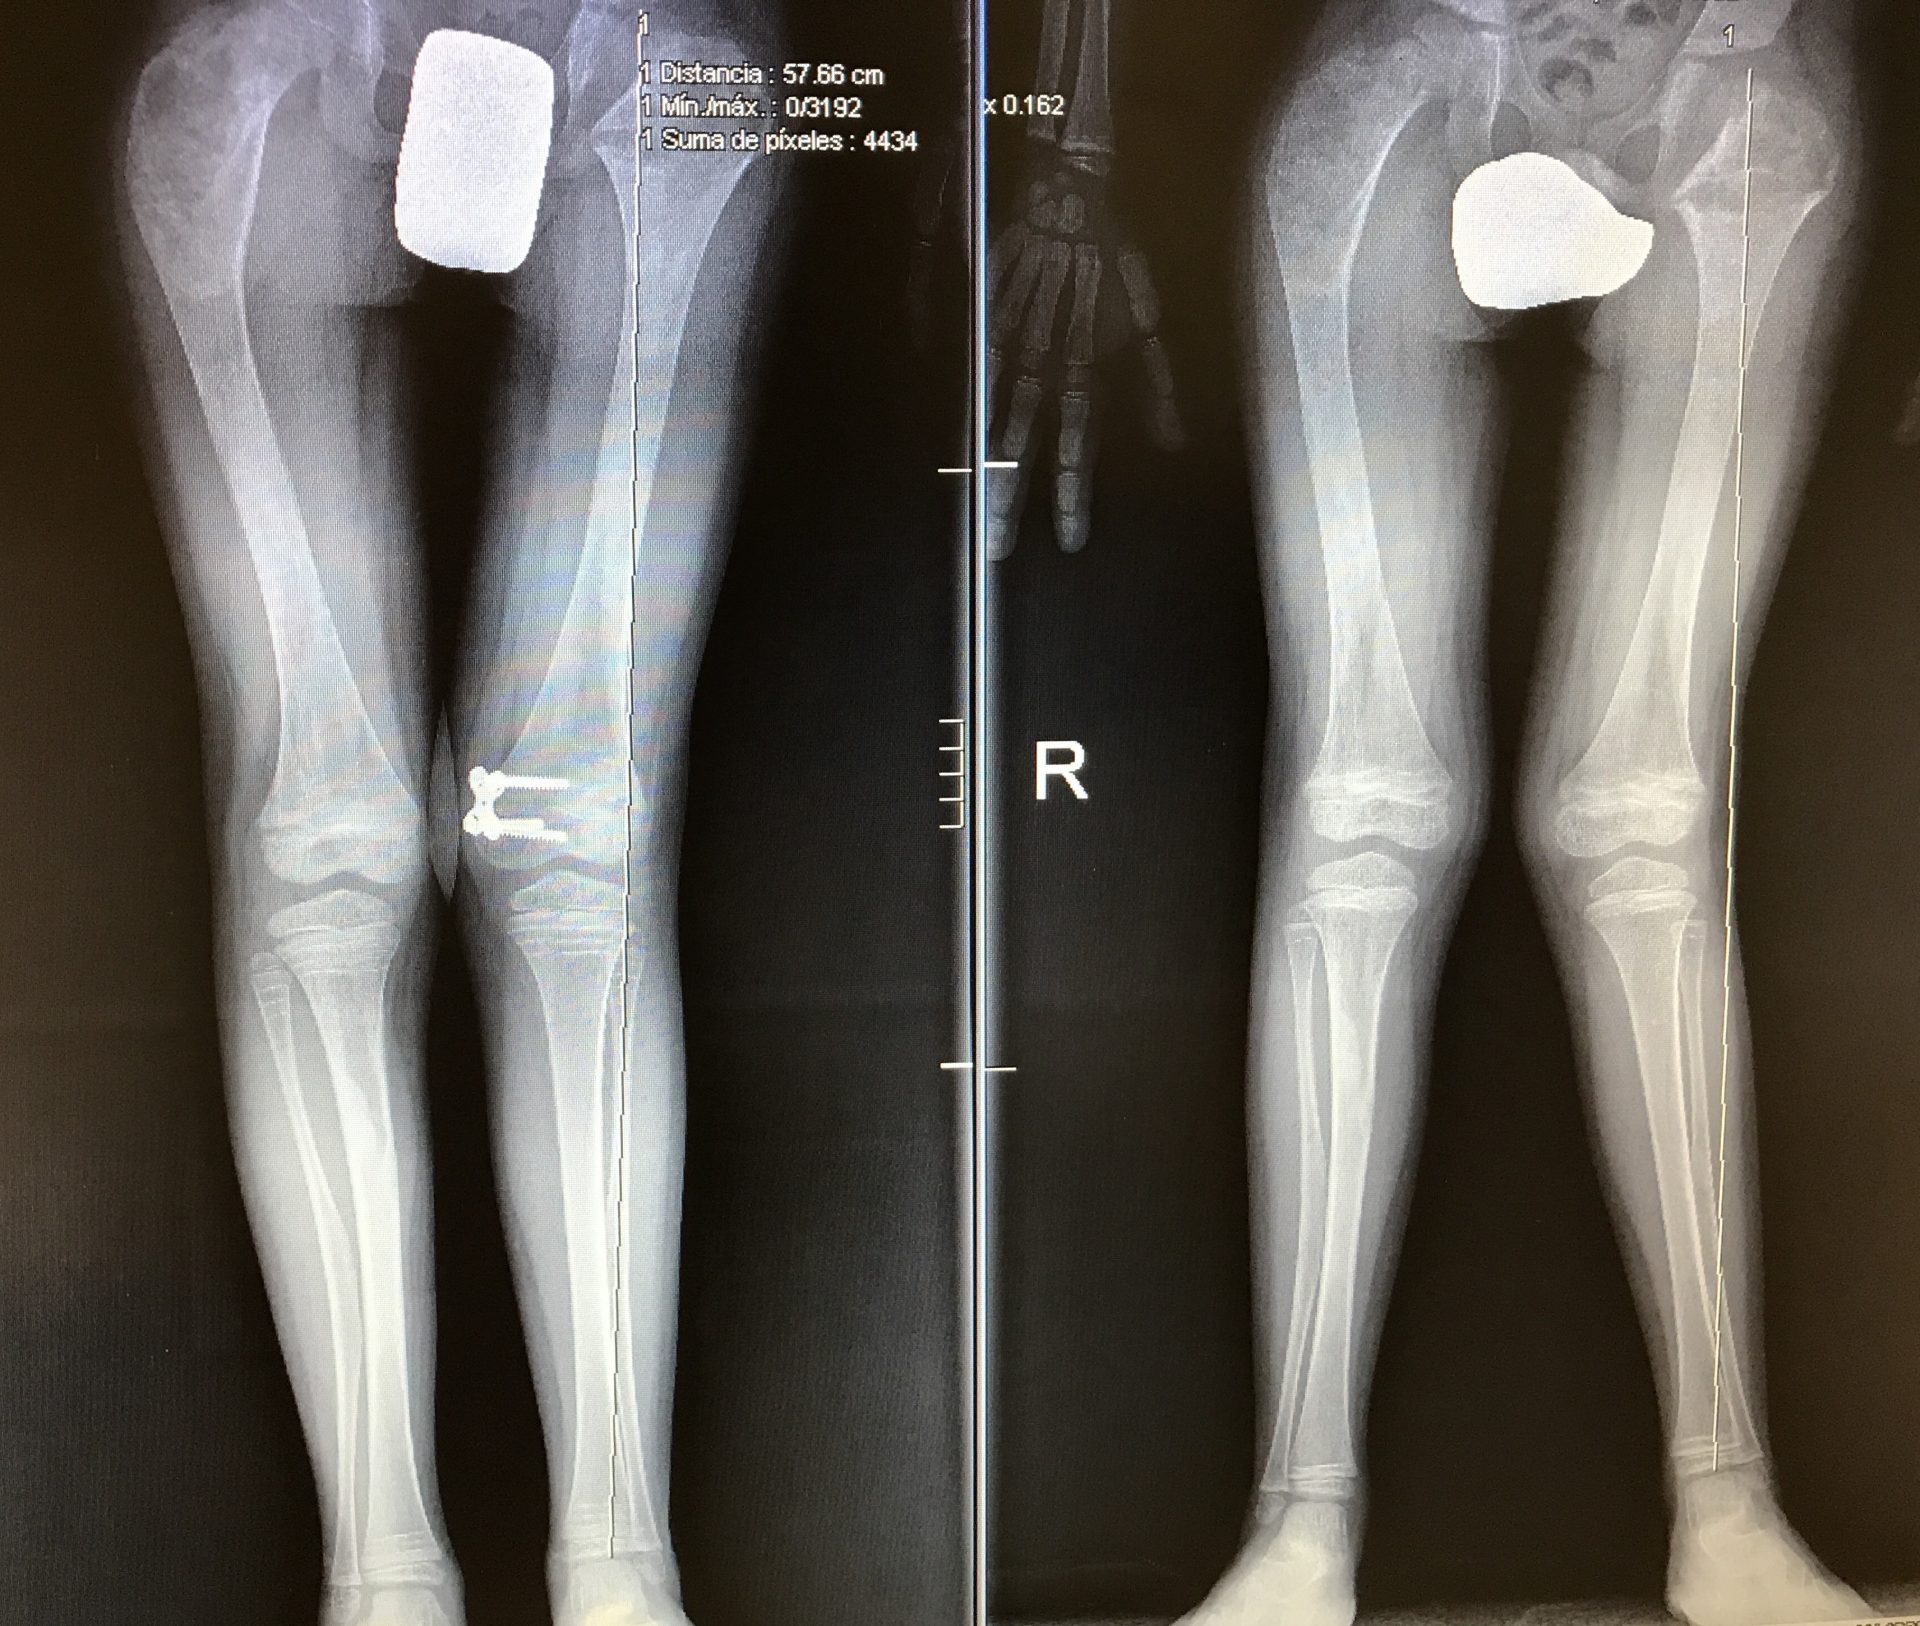

FullSizeRender 11